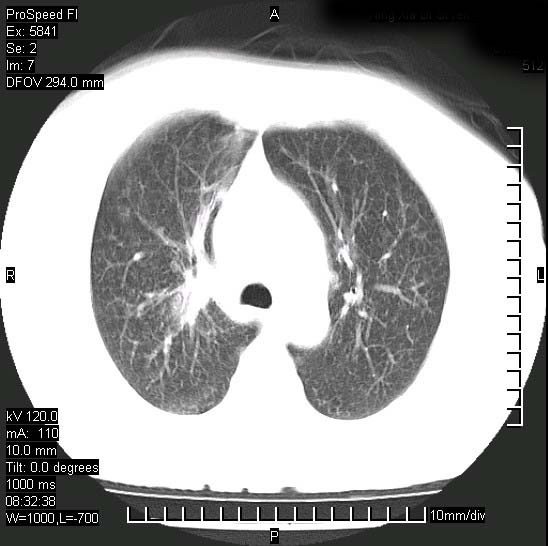

胸痛,咳嗽,气短一周,无发热。右上肺见一结节灶,边缘刺角,内见多个小钙化结节。考虑结核球?肿瘤? 余无异常没有上传。

考虑右肺上叶继发性肺结核,结核球形成。

支持结核球诊断但建议薄扫

胸膜是受侵的,考虑感染,结核球可能性大

考虑结核球,并胸膜局限性增厚!!

为什么不考虑肺癌????????????